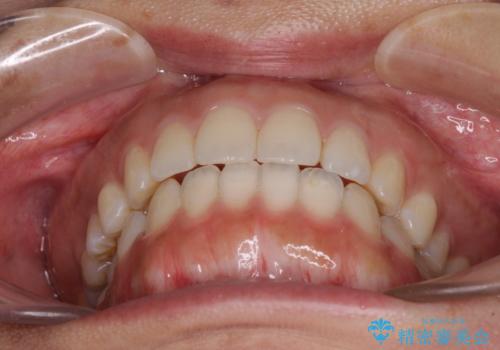

全く目立たないワイヤー矯正 上下リンガル矯正

- 上下の前歯のでこぼこを気にして来院された患者様です。

結婚式が近いこともあり、全く目立たない裏側矯正により口元を整えることとしました。

下顎が左側にずれているため、裏側矯正ということもあり咬み合わせを整えるのに時間がかかってしまいました。